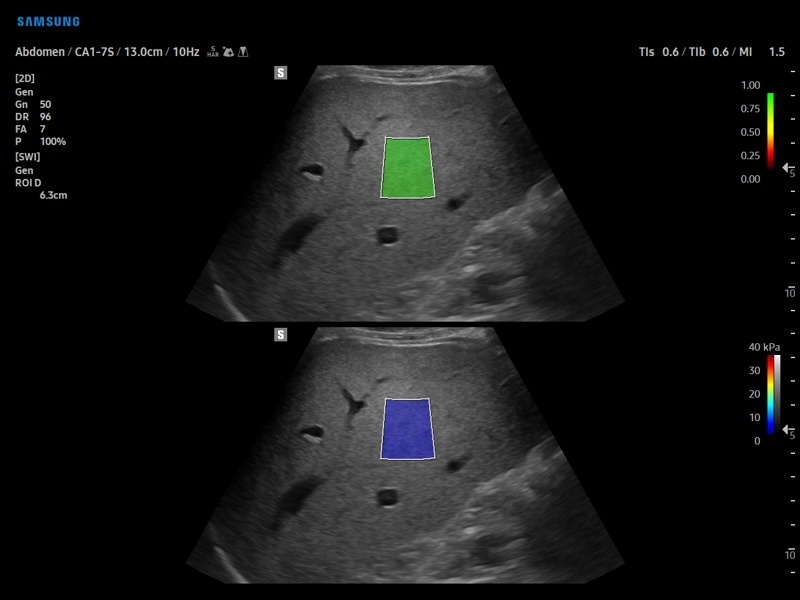

• S-Shearwave Imaging для эластографии сдвиговой волной

Компрессионная, Сдвиговая

Эластография сдвиговой волной/Эластометрия:

Да

Компрессионная эластография:

• Модуль Elastoscan - программы эластографии для исследований щитовидной железы, молочной железы у женщин и предстательной железы у мужчин.

• Модуль E-Strain – полуколичественный анализ индекса Strain Ratio в режиме компресионной эластографии.

• Модуль S-Shearwave imaging – программа цветовой сдвиговой эластографии позволяющая автоматически определять индекс жесткости различных участков исследуемого объекта в кПа или м/с, получая при это еще и индекс достоверности данных RMI.